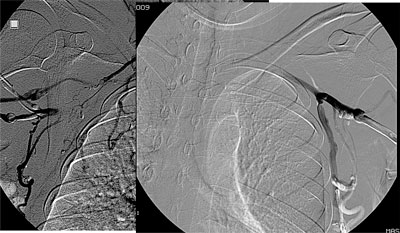

Paciente feminino, 50 anos, portadora de insuficiencia renal terminal em tratamento em outra instituição, já com fibrose peritoneal e com múltiplas confecções de fístulas arteriovenosas nos membros superiores sendo a última fístula um enxerto bráquio-jugular direito pois a paciente apresentava oclusão das veias subclávias. Tal enxerto arteriovenoso havia trombosado há 5 dias e não ocorreu sucesso na tentativa de trombectomia cirúrgica. Sem realizar diálise a paciente apresentava sinais de uremia (confisão mental e sonolência), anasarca e tinha potássio de 8.0mg/dl quando foi solicitado nossa avaliação nesta outra instituição. Encaminhado a paciente para sala de ultrassonografia onde foi avaliado as veias jugulares, subclávias e femorais, todas mostraram-se ocluídas. Em virtude da urgência dialítica foi implantado um cateter de duplo lúmen na veia poplítea direita guiado por ultrassonografia. Foi realizado hemodiálise por três dias consecutivos, sendo alcançado fluxo de 150 ml/min. Houve melhora clínica e dos níveis urêmicos e de potássio. A paciente foi então transferida para nossa instituição onde foi submetida à flebografia dos membros superiores, não ocorrendo opacificação das veias axilares, subclávias e veia cava superior. Realizado tentativa de recanalizacão da veia femoral direita sem sucesso. Optado pelo implante translombar de cateter de duplo lúmen tipo permcath. O procedimento transcorreu sem intercorrências e a paciente teve alta no dia seguinte. Após 9 meses de acompanhamento a paciente apresentou infecção do cateter sendo trocado por um novo cateter via translombar.